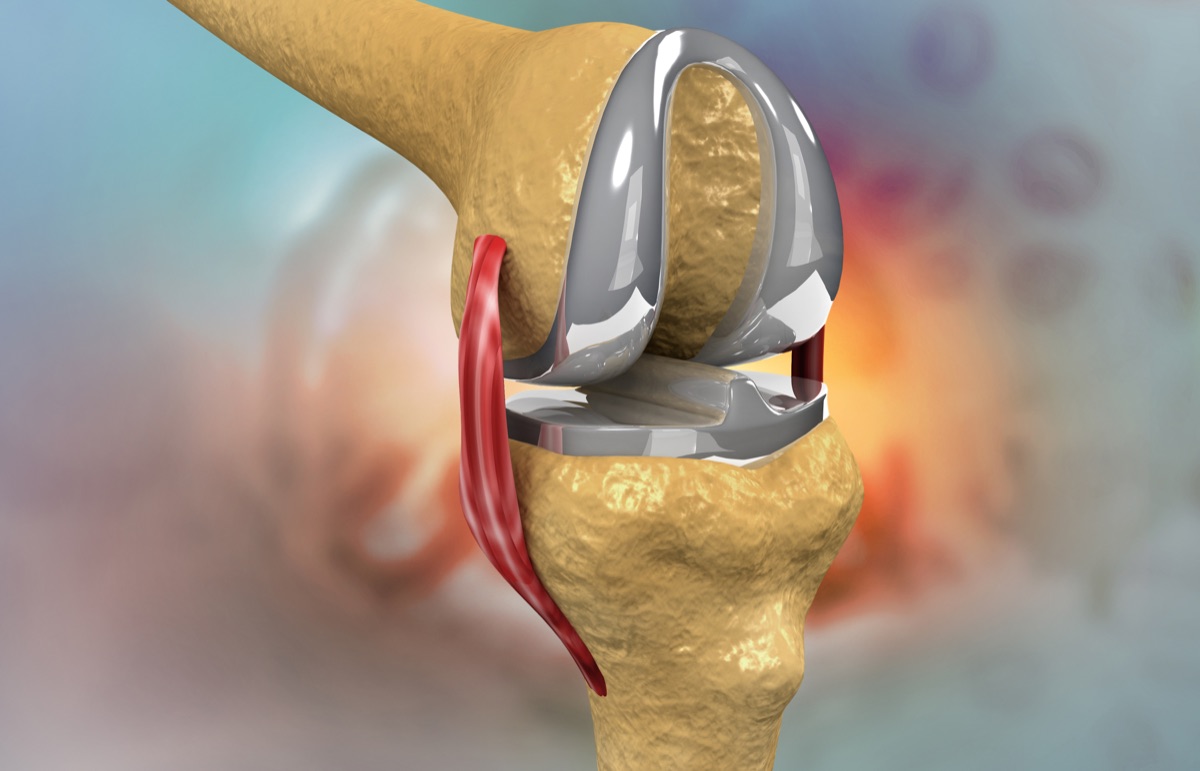

The knee is the largest joint in your body, formed by three bones—the femur (thighbone), tibia (shinbone), and patella (kneecap). These are connected by ligaments, cushioned by cartilage, and surrounded by the joint capsule.

Knee replacement becomes necessary when cartilage protecting the joint wears away, causing bone-on-bone contact that leads to severe pain and limited mobility.

Implant Technology

Compare the leading companies behind knee replacement implants and their innovative technologies.